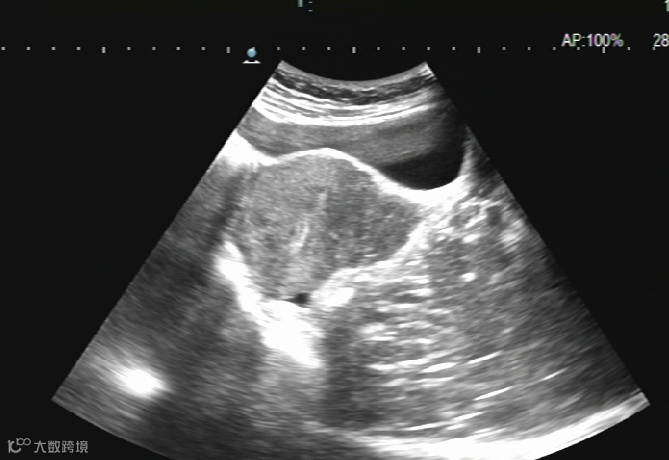

卵巢巧克力囊肿硬化治疗:

治疗前

治疗后